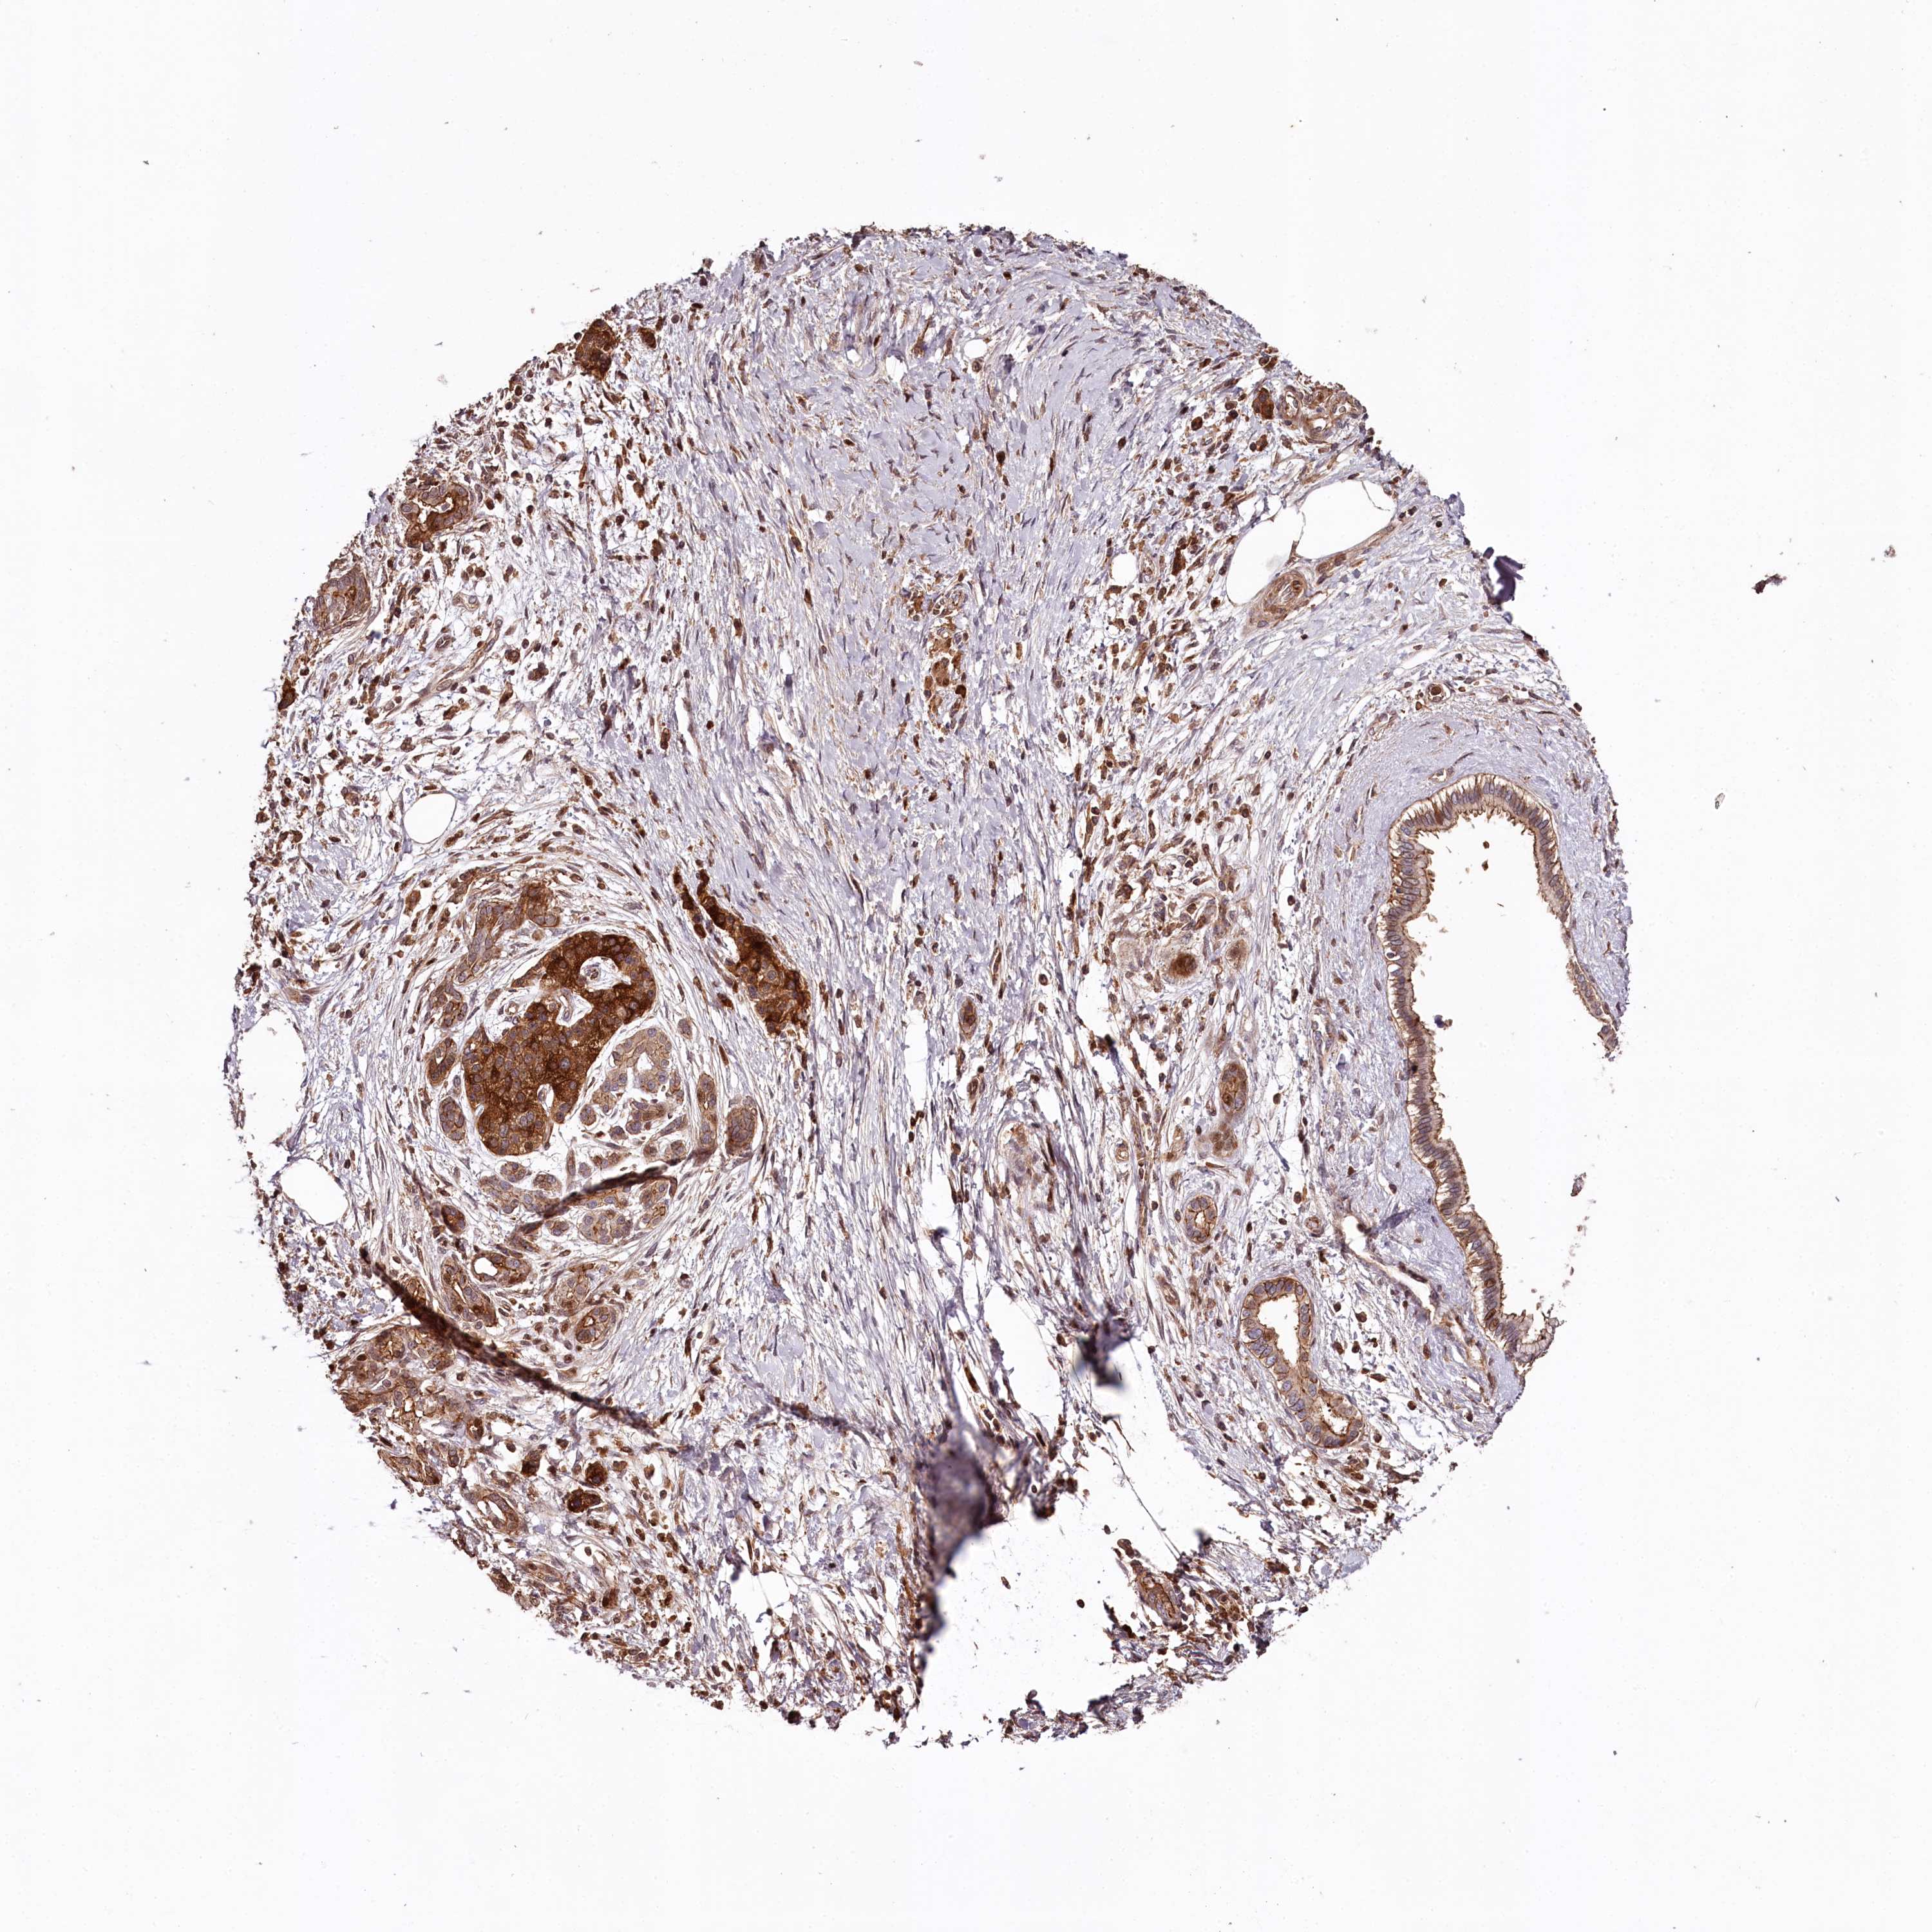

PANCREATIC CANCER - Protein expressioni

A mouse-over function shows sample information and annotation data. Click on an image to view it in a full screen mode. Samples can be filtered based on level of antibody staining by selecting one or several of the following categories: high, medium, low and not detected. The assay and annotation is described here.

Note that samples used for immunohistochemistry by the Human Protein Atlas do not correspond to samples in the TCGA dataset.

Antibody stainingi

Antibody staining in the annotated cell types in the current human tissue is reported as not detected, low, medium, or high, based on conventional immunohistochemistry profiling in selected tissues. This score is based on the combination of the staining intensity and fraction of stained cells.

Each image is clickable and will lead to virtual microscopy that enables deeper exploration of all samples and also displays staining intensity scores, fraction scores and subcellular localization as well as patient and tissue information for each sample.

Antibody HPA038061

Staining

High

Medium

Low

Not detected

Intensity

Strong

Moderate

Weak

Negative

Quantity

>75%

75%-25%

<25%

None

Location

Nuclear

Cytoplasmic/membranous

Cytoplasmic/membranous,nuclear

Adenocarcinoma, NOS